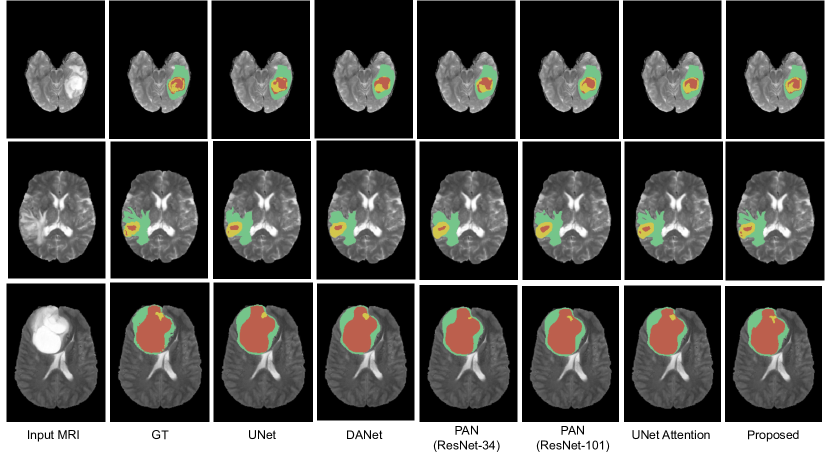

Similar results are observed on the segmentations obtained in the BRATS’18 images (Fig. 5). Particularly, we can see that the proposed network obtains finer details than the other architectures. For example, small ramifications on the oedema (in green) are better captured by the proposed model (second row). Likewise, segmentation of necrotic areas (in red) achieved by our method is closer to the ground truth, specially when the region has a complex shape (first row). These visual results indicate that our approach can successfully recover finer segmentation details, while avoiding getting distracted in ambiguous regions. The selective integration of spatial information and among channel maps followed by a guided attention module helps to capture context information. This demonstrates that the proposed multi-scale guided attention model can efficiently encode complimentary information to accurately segment medical images.

Refer to caption

Figure 5: Results on three subjects on the BRATS Challenge dataset. In these figures, the following tumor structures are depicted: oedema (green), enhancing core (yellow) and necrotic or tumor core (red).